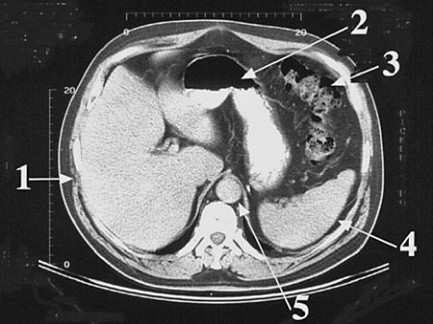

Arrow 4 in following figure, is pointing to which of the following structures?

1. abdominal aorta

2. colon

3. liver

4. spleen

5. stomach

Answer(s): D

The spleen (arrow 4) lies to the left of the abdominal cavity. It is in contact with the left side of the stomach (arrow 2) and lodges against the left paravertebral gutter. The abdominal aorta (choice A, arrow 5) is seen as the circular structure immediately anterior to the vertebra. The colon (choice B, arrow 3) is the convoluted structure to the left anterior aspect of the abdominal cavity. The large liver (choice C, arrow 1) occupies most of the right side of the abdominal cavity. The stomach (choice E, arrow 2) is located between the colon and the liver, and in this case, contains liquid contrast material.